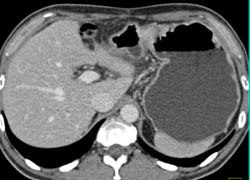

Diagnosis

Gastric Cancer